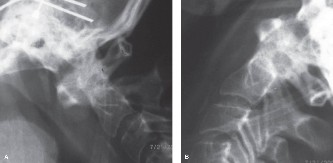

Determine the most appropriate treatment of different types of Hangman’s fractures? CASE 14 A 70-year-old retired, funeral director presents with symptoms of right upper extremity numbness and weakness. He reports that he developed acute neck and right upper arm pain while undergoing a dental procedure. Treatment so far has been nonsteroidal anti-inflammatory medication and physical therapy with cervical traction. While his pain improved with this course of treatment, he has ongoing paresthesias radiating into his right hand and weakness affecting his right upper extremity. Figures 1–20 and 1–21 show a midsagittal and axial image through C6–7, respectively.

Figure 1–20

Figure 1–21

The correct answer is (A). Considering the patient’s complaints and the imaging, he most likely has radiculopathy, probably secondary to a disc-osteophyte complex associated with foraminal stenosis at the C6–7 level. There is no suggestion in the history of walking imbalance or dexterity issues in the upper extremities. Thus, a diagnosis of myelopathy is less likely. Furthermore, the degree of spinal compression is mild and not likely (though not impossible) to cause spinal cord dysfunction. An intradural tumor would have a different MRI appearance, likely demonstrating an area of high signal within the parenchymal tissue of the spinal cord itself. A central cord syndrome is an acute spinal cord injury with upper extremities being affected more than lower extremities.

The correct answer is (C). The patient has nerve root compression at the C6–7 level, which would affect the exiting C7 nerve. Weakness of right elbow extension and wrist flexion with sensory loss of the middle finger are the most likely findings.

The correct answer is (D). Both anterior and posterior surgical approaches have been associated with consistently good clinical outcomes in this patient population having single level radiculopathy from foraminal stenosis secondary to a disc-osteophyte complex. Objectives: Did you learn...? Recognize the clinical presentation of cervical radiculopathy associated with a disc-osteophyte complex?